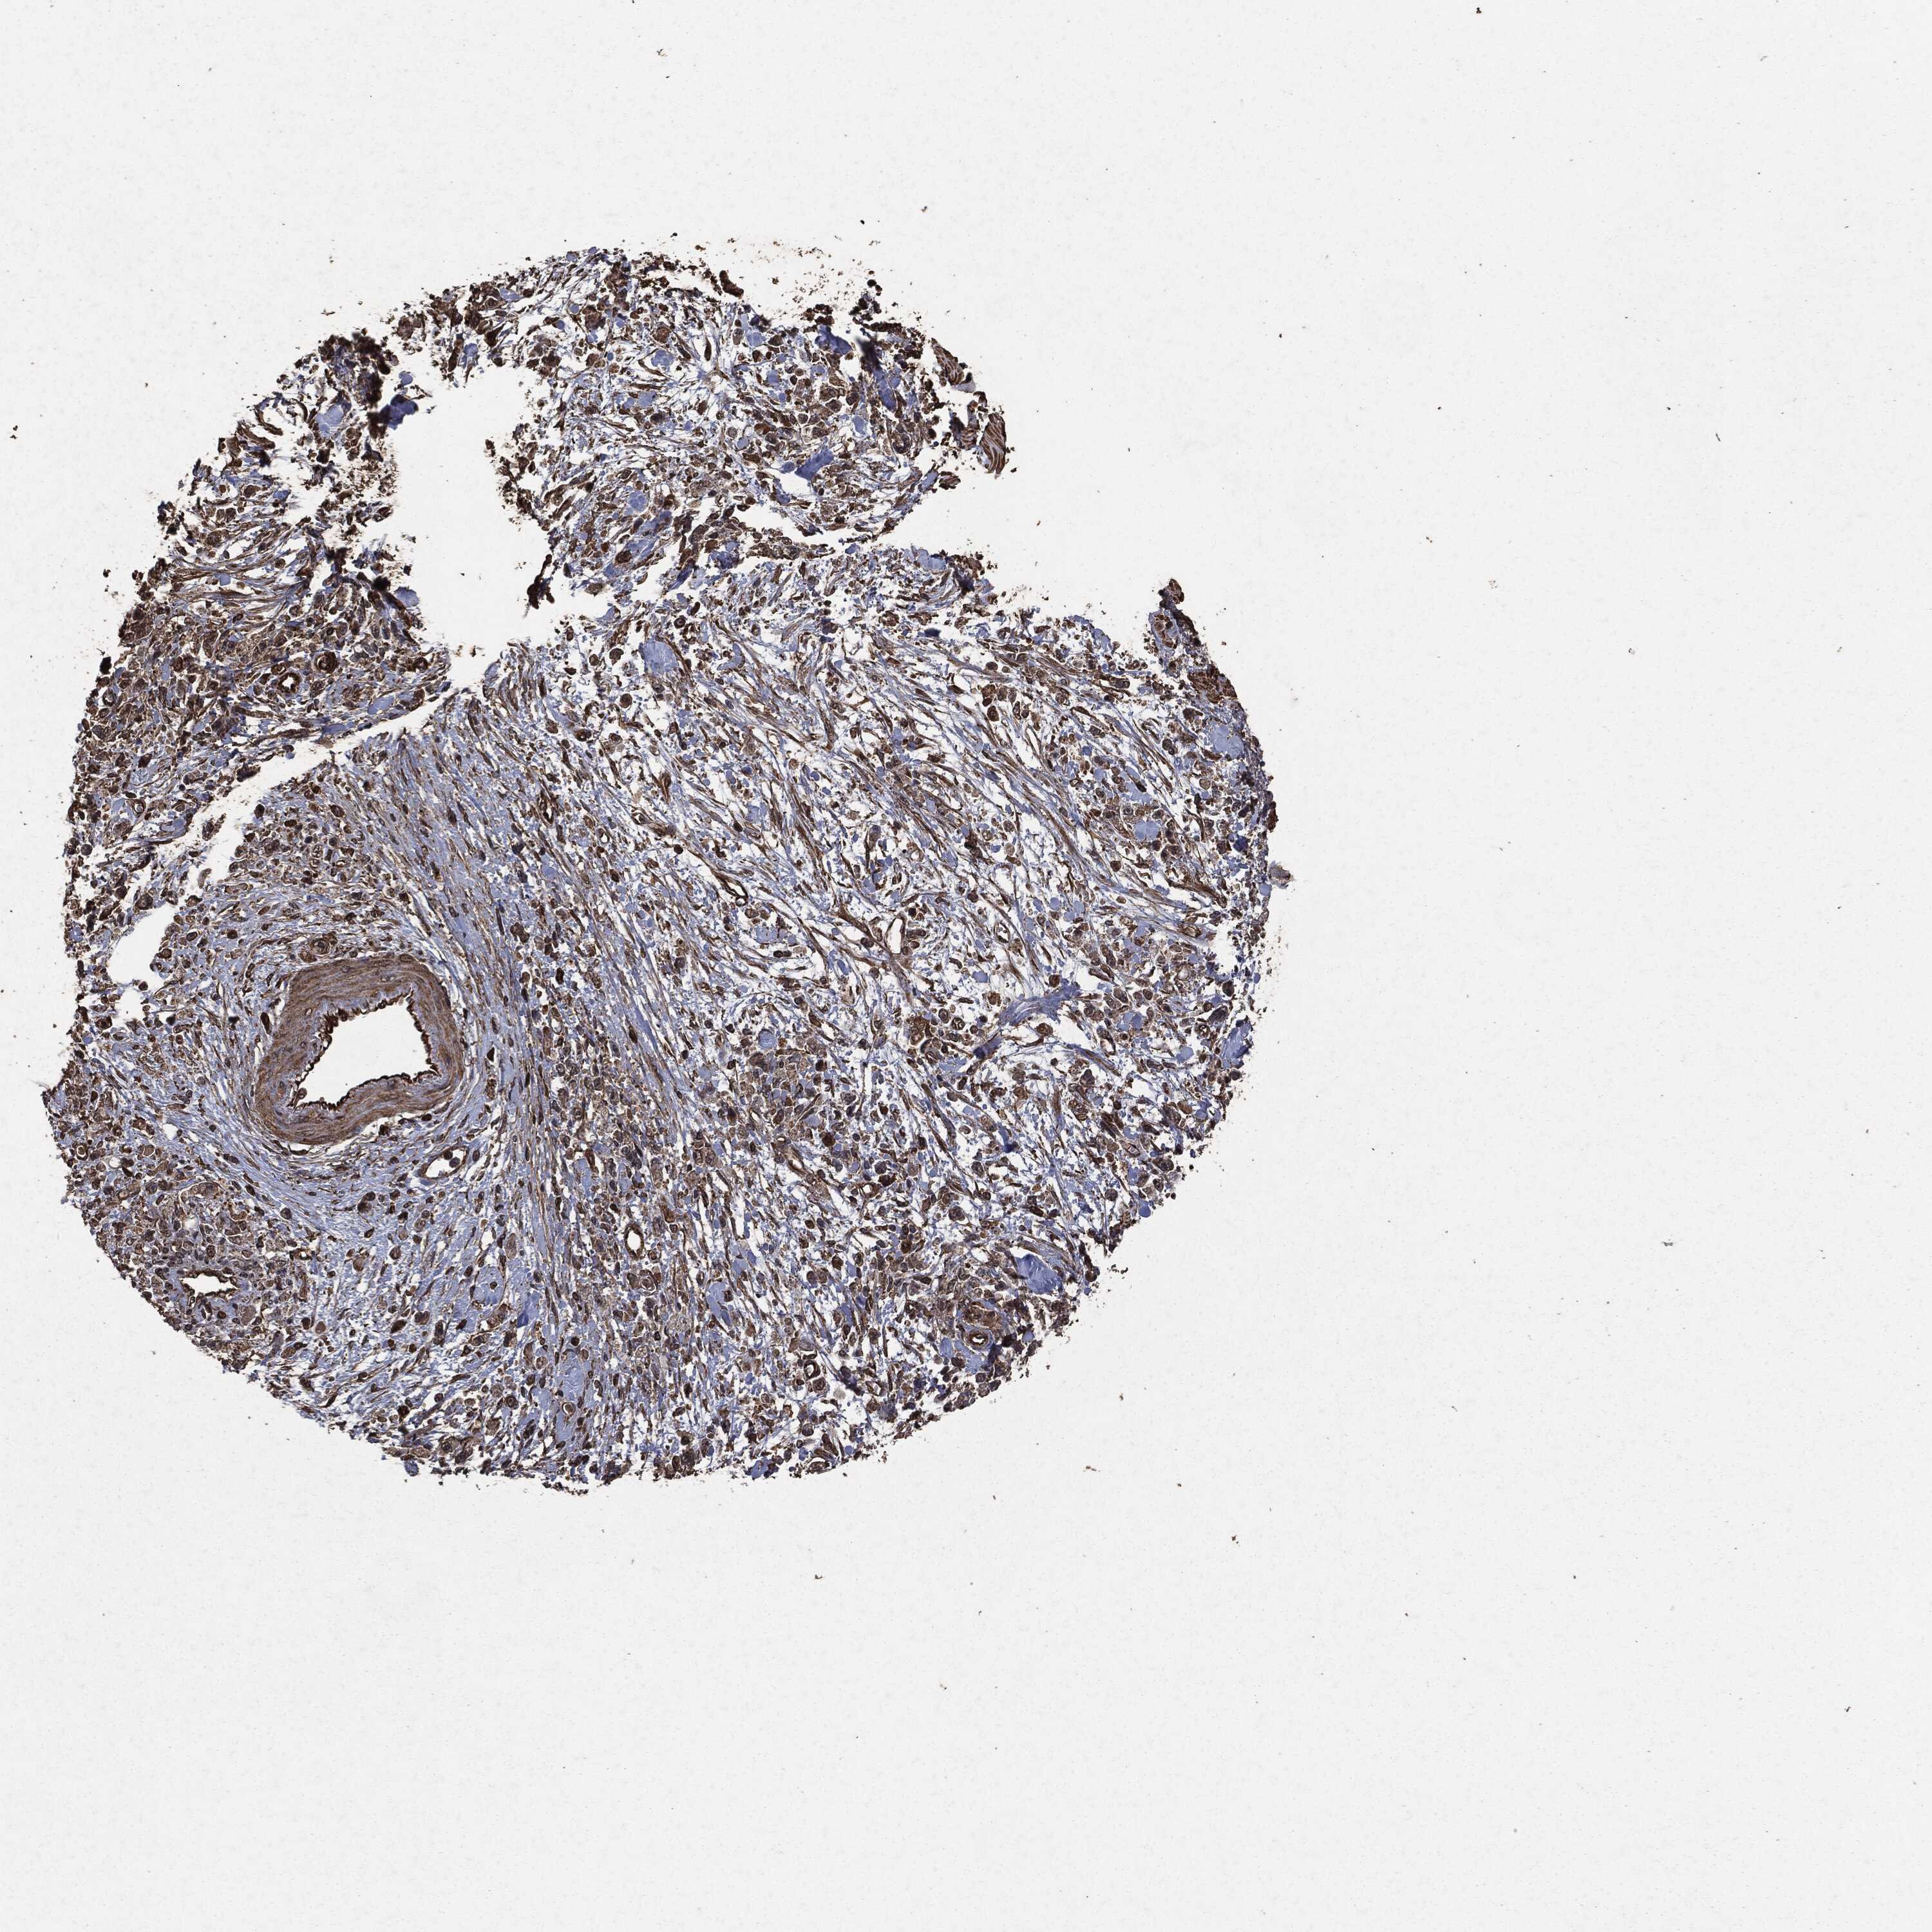

STOMACH CANCER - Protein expressioni

A mouse-over function shows sample information and annotation data. Click on an image to view it in a full screen mode. Samples can be filtered based on level of antibody staining by selecting one or several of the following categories: high, medium, low and not detected. The assay and annotation is described here.

Note that samples used for immunohistochemistry by the Human Protein Atlas do not correspond to samples in the TCGA dataset.

Antibody stainingi

Antibody staining in the annotated cell types in the current human tissue is reported as not detected, low, medium, or high, based on conventional immunohistochemistry profiling in selected tissues. This score is based on the combination of the staining intensity and fraction of stained cells.

Each image is clickable and will lead to virtual microscopy that enables deeper exploration of all samples and also displays staining intensity scores, fraction scores and subcellular localization as well as patient and tissue information for each sample.

HPA049830

CAB002015

CAB080330

CAB080331

CAB080332

Staining

High

Medium

Low

Not detected

Intensity

Strong

Moderate

Weak

Negative

Quantity

>75%

75%-25%

<25%

None

Location

Nuclear

Cytoplasmic/membranous

Cytoplasmic/membranous,nuclear

Adenocarcinoma, NOS

Adenocarcinoma, High grade